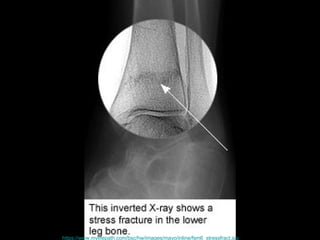

壓力性骨折 Stress Fracture 疲勞骨折 Fatigue fracture   骨質不良性骨折 Insufficiency fracture http://www.emedicine.com/radio/topic783.htm

http://www.med.umich.edu/1libr/sma/stressfx.gif

https://www.mylifepath.com/bsc/hw/images/mayo/inline/fsm6_stressfract.jpg